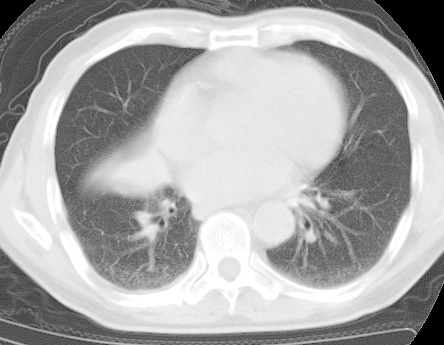

标题: CT24032:男65岁,咳嗽,吸烟20余年,无发热,咳痰 [打印本页]

标题: CT24032:男65岁,咳嗽,吸烟20余年,无发热,咳痰

考虑右肺中叶不张,请大家发表意见

右肺中叶不张、肺门轮廓增大,占位不除外;建议增强,必要时支气管镜详查。

右肺中叶支气管闭塞,中叶肺不张,右侧肺门见肿块影。中心型肺癌的可能大。建议支气管镜检查。

右中叶体积明显缩小,且其支气管未显示,先考虑:中心型肺癌班右中叶肺不张。

建议:支气管镜检查。

考虑右肺中叶中央型肺癌并右肺中叶肺不张;建议:行纤支镜检查。

右肺门旁类圆形肿块影,右肺中叶不张,建议纤支镜检查。

1右肺门旁类圆形肿块影,右肺中叶不张,建议纤支镜检查

2右侧胸膜增厚,右侧叶间胸膜区钙化

3右肺下叶小囊状透亮影考虑肺气肿